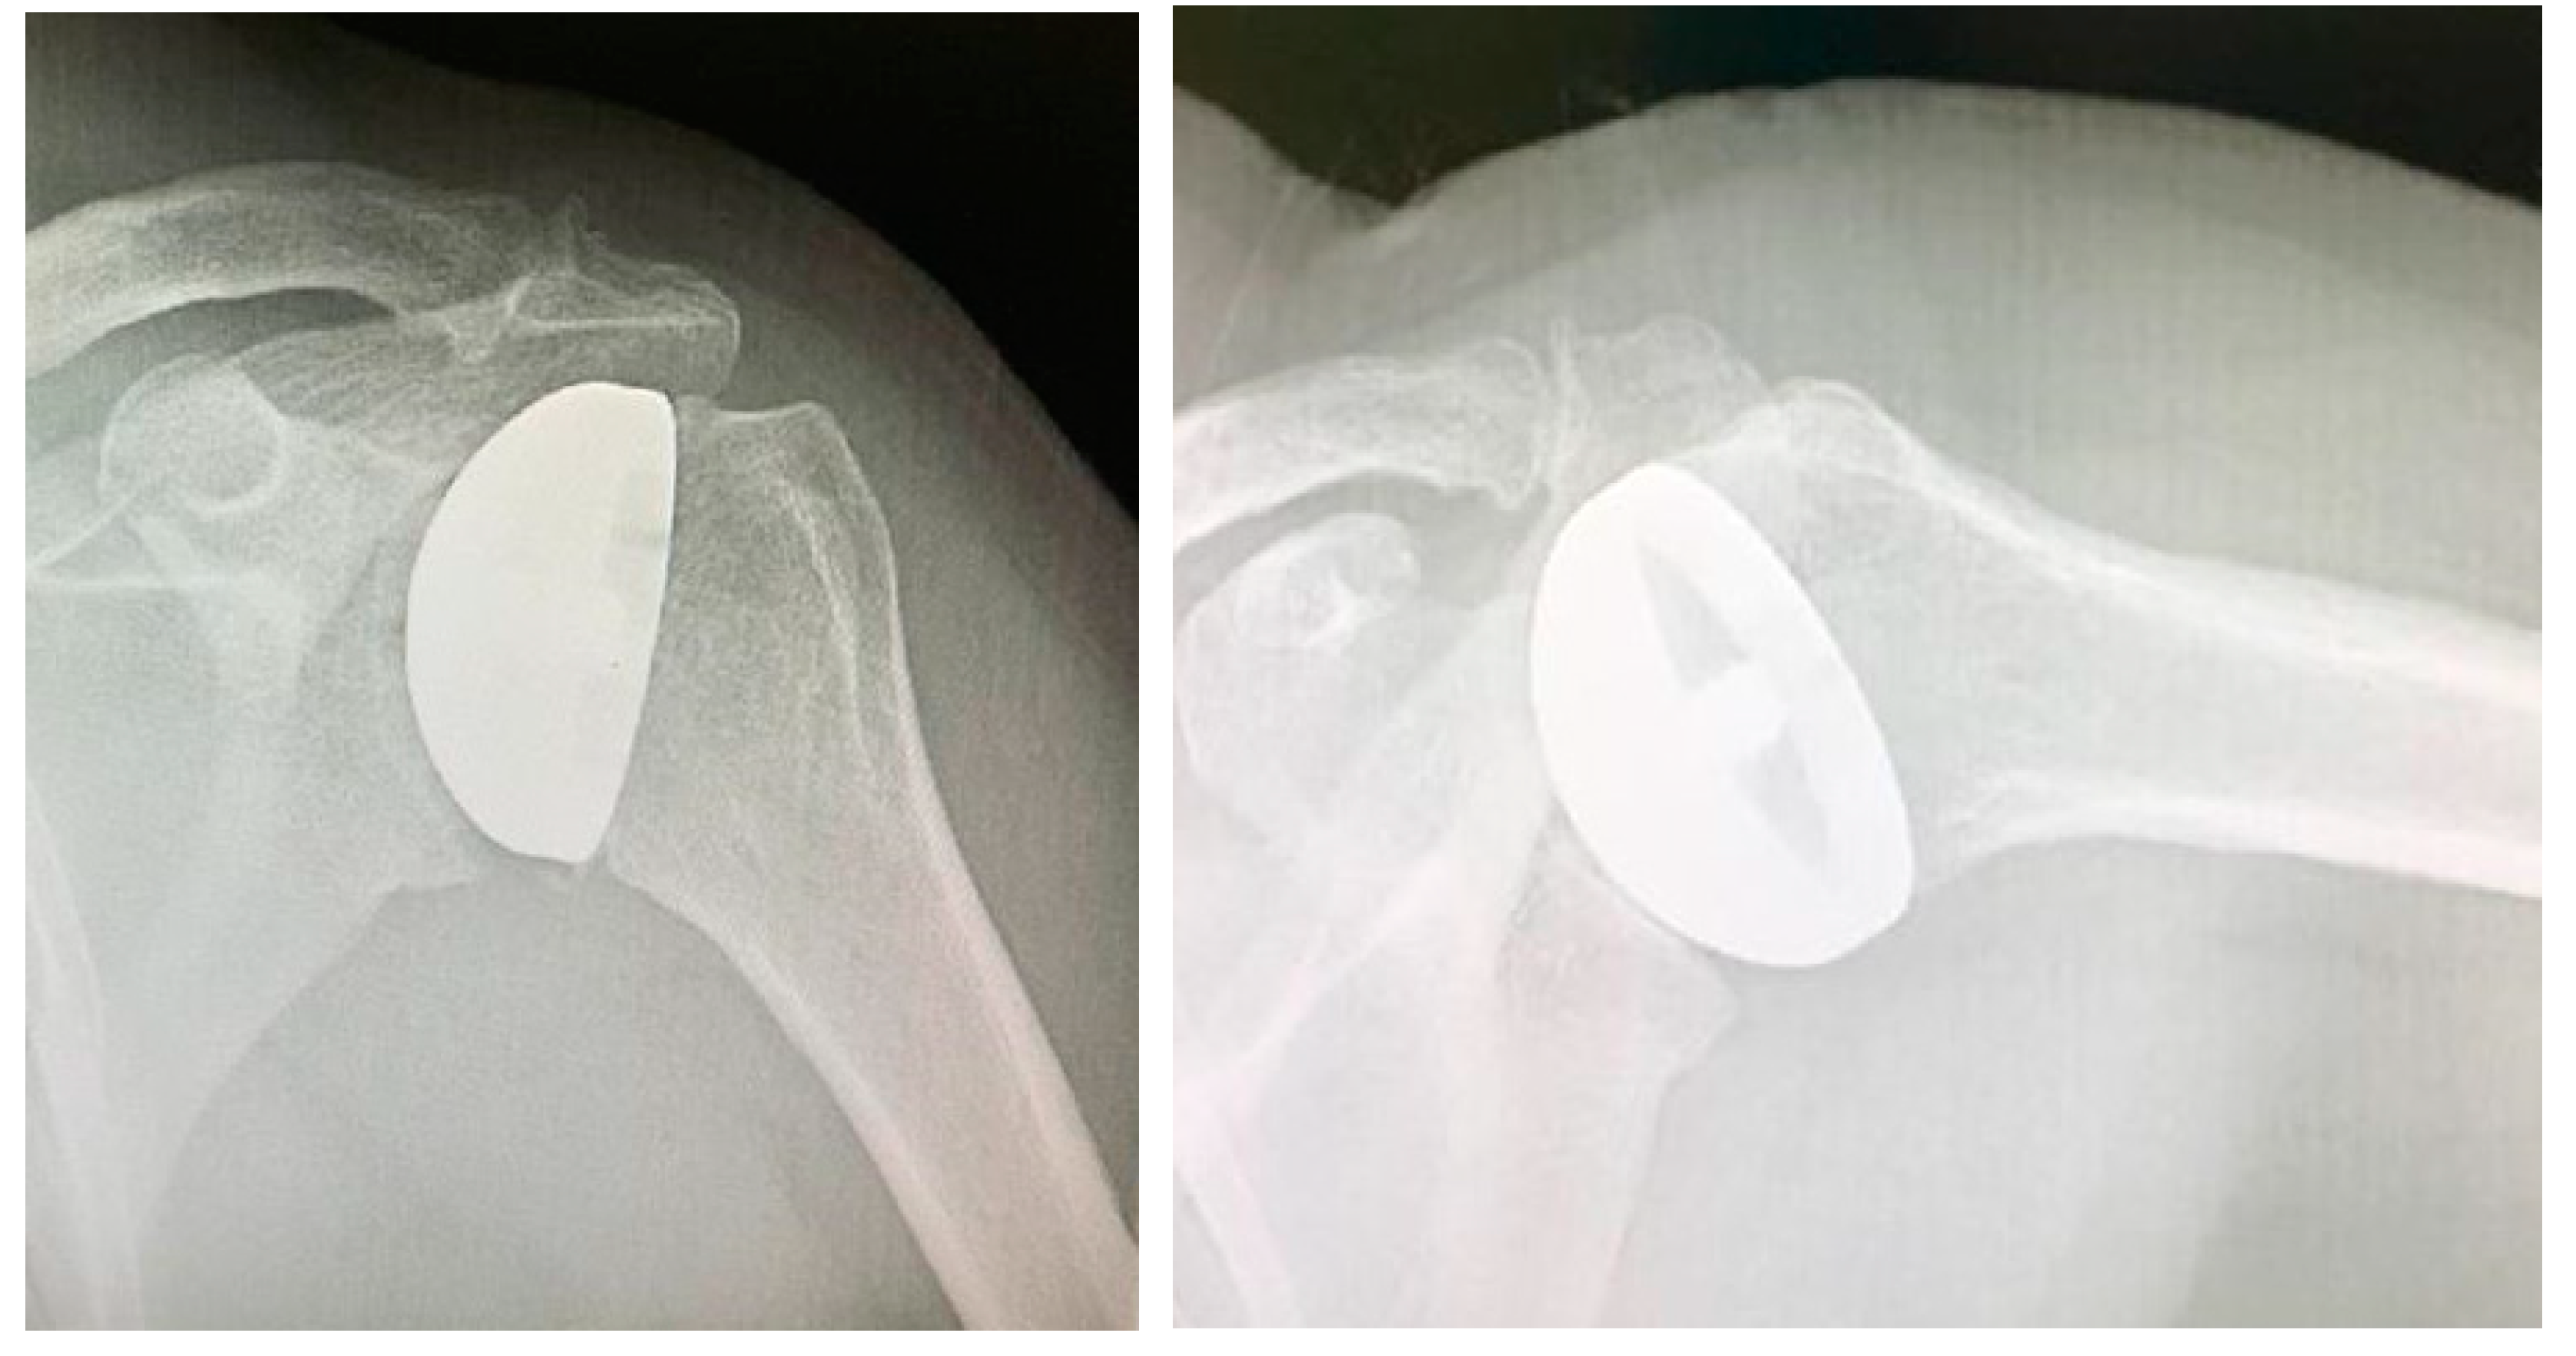

Figure 2. Avascular necrosis of the humeral head treated with a resurfacing prosthesis.

Surgical procedure. All the surgeries were performed by the senior Author (S.G.), implanting a Durom Shoulder Cup (Zimmer Biomet, Warsaw, Indiana, USA), a Copeland Humeral Resurfacing Head Surgery (Zimmer Biomet, Warsaw, Indiana, USA) or a SMR Resurfacing Shoulder Prosthesis System (Lima Corporate, Udine, Italy). All patients were pre-operatively evaluated through a clinical examination, plain radiographs in antero-posterior and axillay view, computed tomography scan and magnetic resonance imaging (Figure 3) in order to determine the correct indication to HRA.